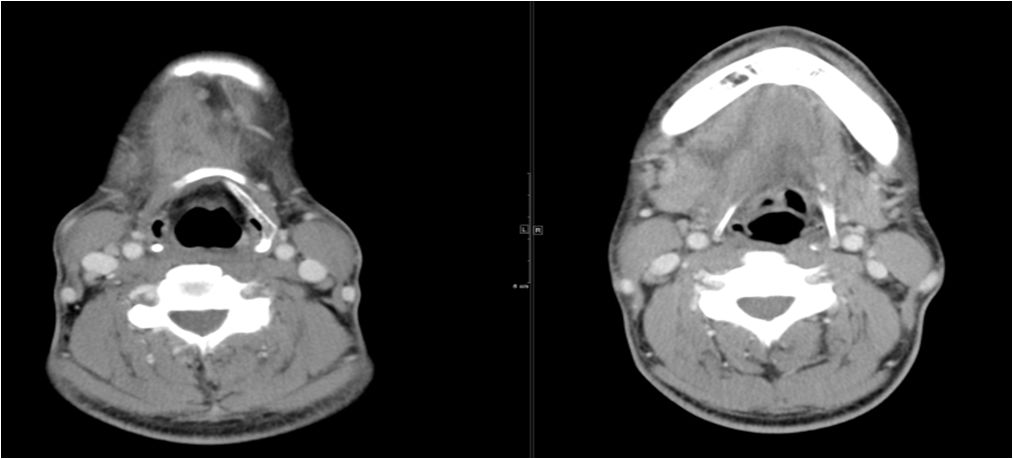

15 多间隙受累

(1)左下后牙疼痛11天余,颈部肿胀10天。

(2)右侧颌面部弥漫性肿胀1月余。